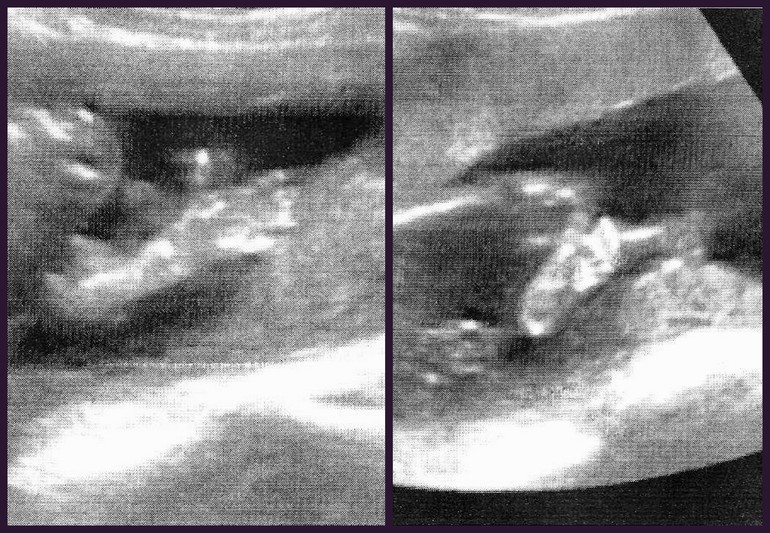

Ну и на память наши ручки-ножки на 20 неделе ))